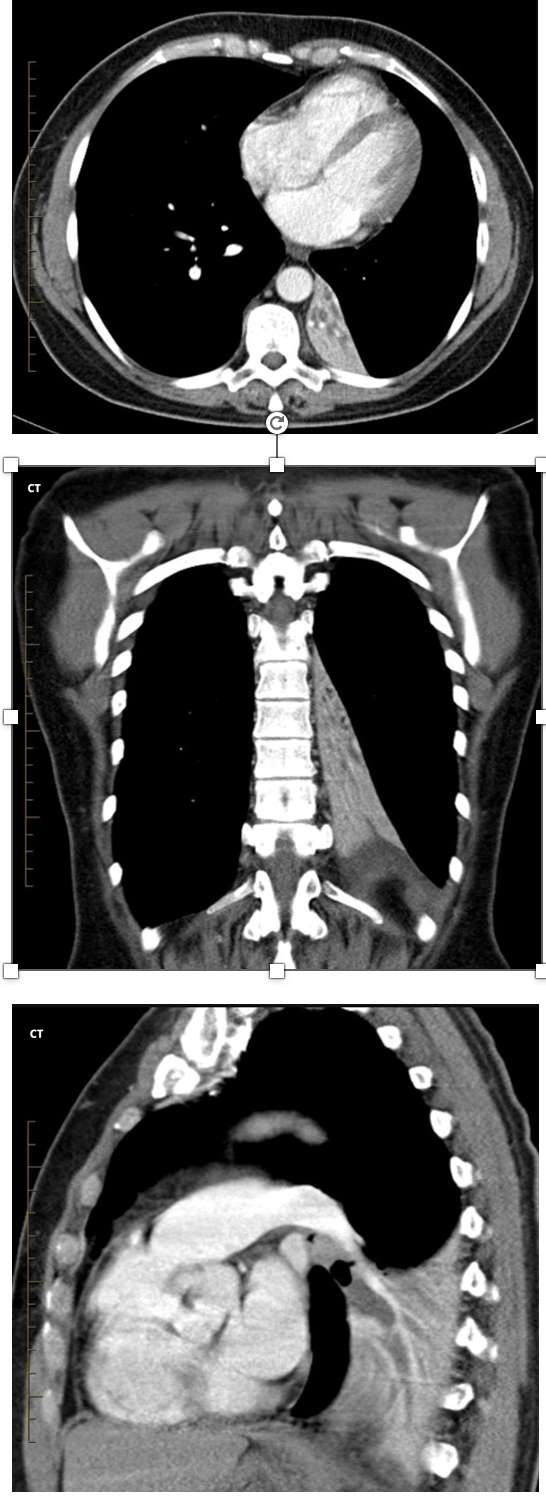

Q

A

Retrocardiac sail sign: Triangular opacity in posteromedial L lung

Double cardiac contour

Inferior displacement of L hilum

Flat waist sign: flattening of L heart border

Obscured L hemidiaphragm

Obscured descending aorta

Preserved L heart border (which is contacted by the lingula of LUL)

Inferior displacement of oblique fissure

Elevation of L hemidiaphragm

Crowding of L ribs

Shift od mediastinum to the left

Lateral CXR:

Triangular opacification in lower posterior chest

Lower thoracic vertebrae appear denser

19

What are the features of LLL collapse on CT scan

Triangular opacification in axial images, thinner at hilum

Oblique fissure rotates posteromedially or posteriorly

Compensatory hyperinflation of LUL